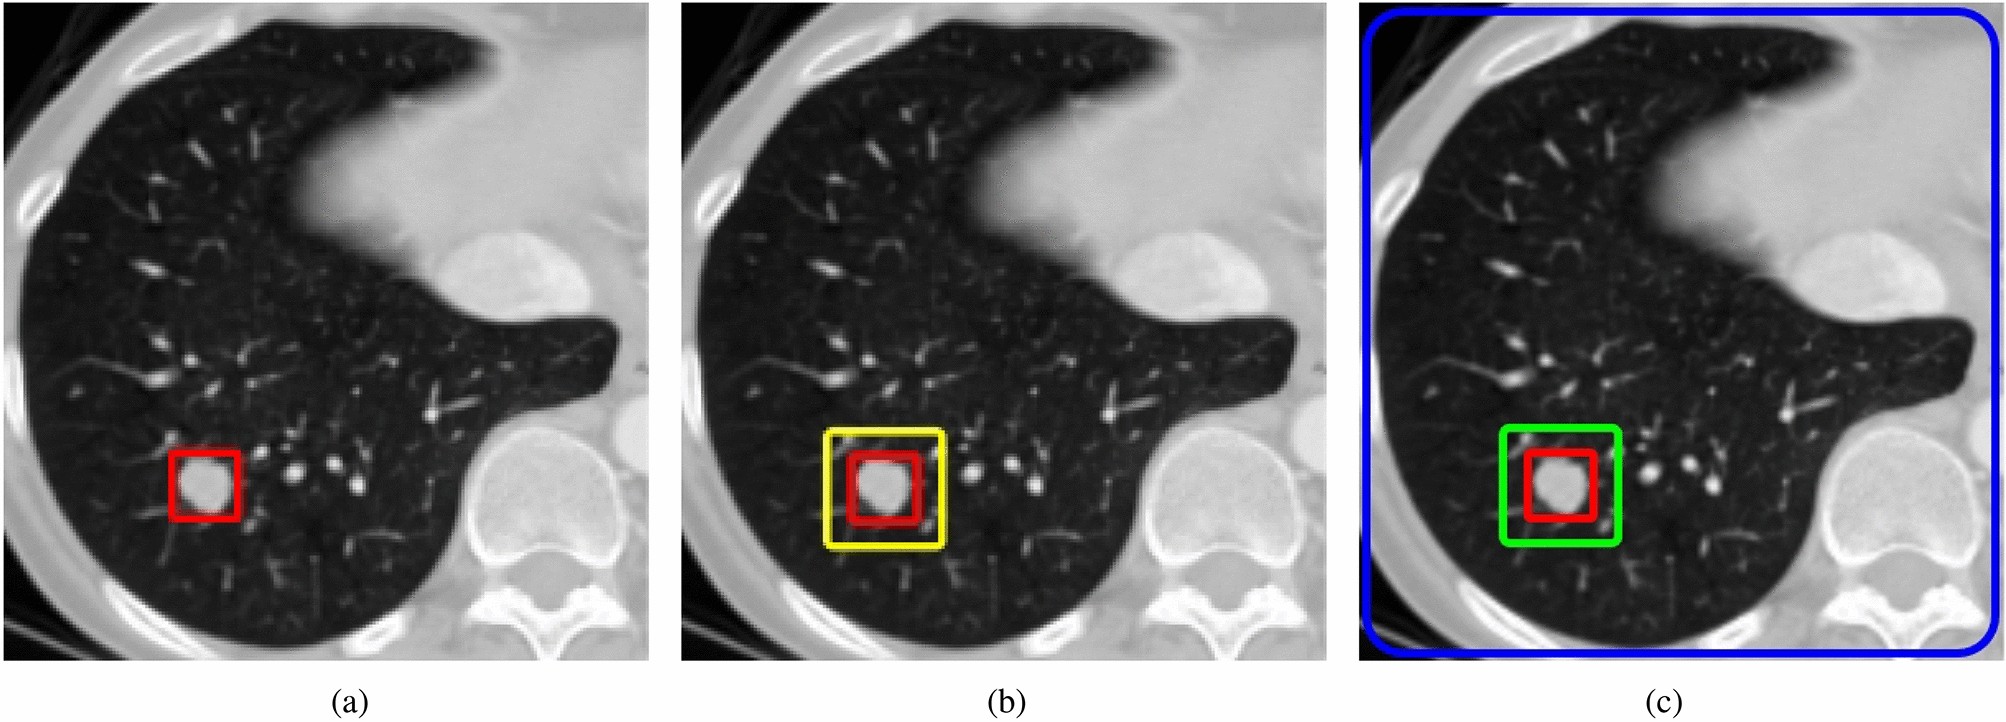

Figure 4

The illustration of target detection by leveraging surrounding contextual information. The JCF module mimics the human visual system by leveraging surrounding contextual information to enhance detection.